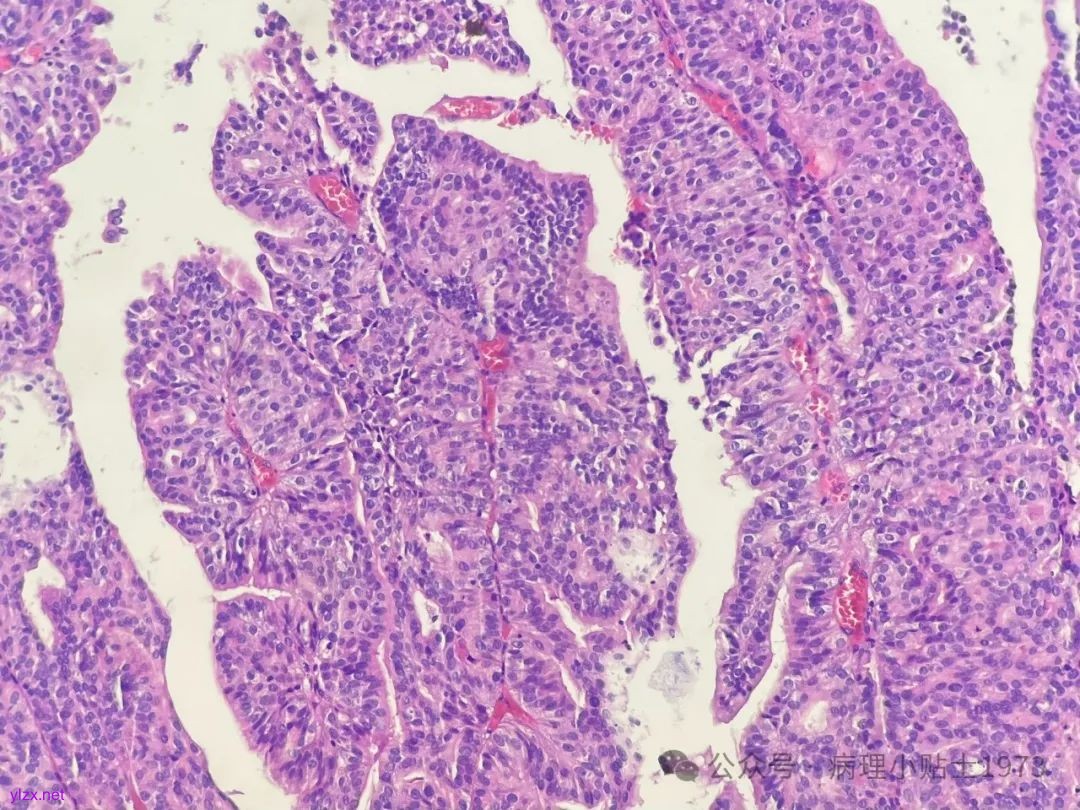

诊断:非浸润性乳头状尿路上皮癌伴显著腺性分化

问题一:本病例出现了显著的腺性分化,不要误诊为单纯的腺癌。仔细寻找,仍然可以见到复层排列的经典尿路上皮癌成分。

问题二:本病例的肿瘤极性轻度紊乱,细胞核轻度到中度异型,部分可见清晰小核仁清晰,凋亡易见,免疫组化弥漫表达p16和CK20(弥漫阳性多见于高级别病变),ki67指数较高。到底该归入低级别还是高级别病变呢?